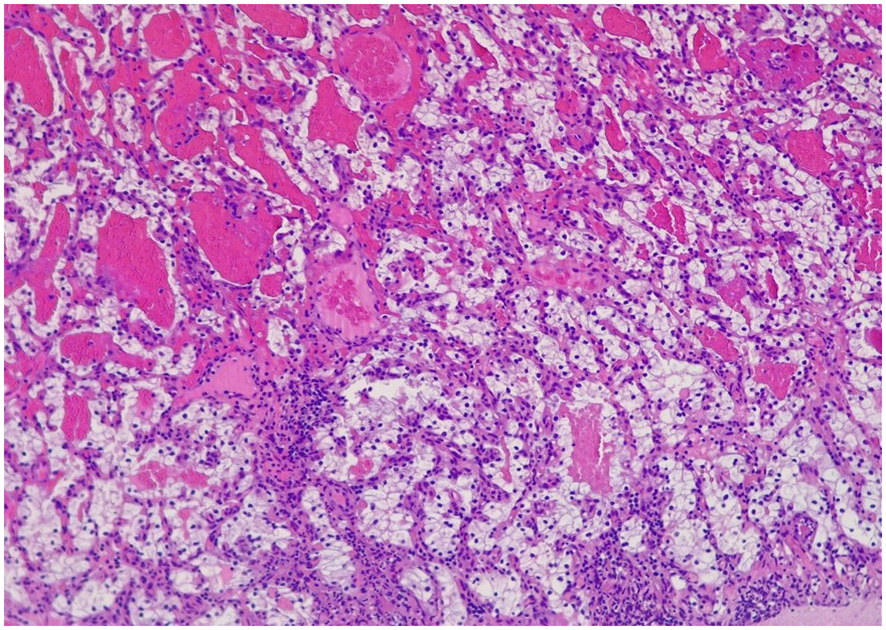

Gastroscopy revealed at the major curve of the gastric body, a 12mm polypodial lesion with pseudopedicled morphology, its surface was ulcerated with blood oozing. In the histological analysis of the gastric polyp, a polypoid formation with an ulcerated surface is described, in which a tumor consisting of cells of different sizes, some dilated, covered by cells with large clear cytoplasms and slightly irregular nuclei, is observed in the lamina propria (Figure 2). Immunohistochemistry of the gastric lesion showed positive staining for CD10 and Keratin CAM5.2 (Figure 3), consistent with metastatic ccRCC. To rule out metastatic recurrence at other body sites, a CT scan was performed following the gastroscopy. The results demonstrated no evidence of metastatic ccRCC elsewhere in the patient’s body.

Figure 2 Polypoid formation that presents on the ulcerated surface, in which a tumor can be seen in the lamina propria made up of glands of different sizes, some dilated, which are covered by cells that have large clear cytoplasms and slightly irregular nuclei with small nucleoli eosinophils. They are separated by an edematous stroma.